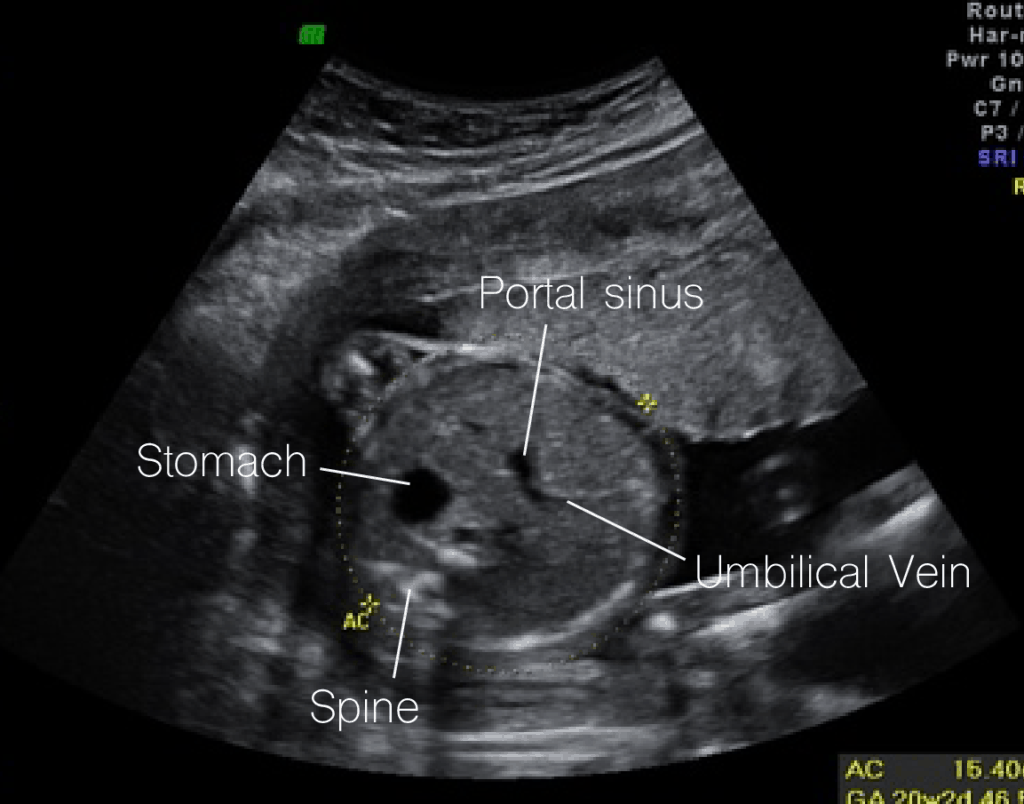

Ultrasound Level 2/TIFA Scan

Ultrasound Level 2/TIFA (Targeted Imaging for Fetal Anomalies) Scan is a comprehensive fetal ultrasound examination typically performed between 18 to 22 weeks of pregnancy. This advanced imaging technique aims to assess the detailed anatomy and development of the fetus, focusing on detecting any potential abnormalities or congenital defects. During the scan, a trained sonographer carefully examines various fetal structures, including the brain, spine, heart, limbs, and internal organs, to ensure they are developing normally. The Level 2/TIFA scan is particularly beneficial for identifying structural anomalies that may require further evaluation or intervention, providing crucial information for expectant parents and healthcare providers to make informed decisions about the management of the pregnancy.